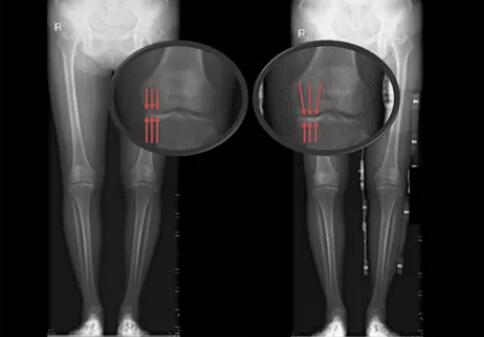

患者未佩戴(左)和佩戴(右)新型矫形支具负重位下肢全长X线片

实验数据结果初步证明,受试者佩戴膝关节内侧减压矫形器后,支撑相后期(膝关节承重的重要周期)膝关节外翻角增大,膝关节内侧力线向外侧转移,膝关节内侧压力降低。

对于早、中期的膝骨关节炎患者,佩戴合理设计的膝关节矫形支具能够矫正下肢力线,从而减轻患髁受力,减轻疼痛、改善患处功能并增加膝关节稳定性。